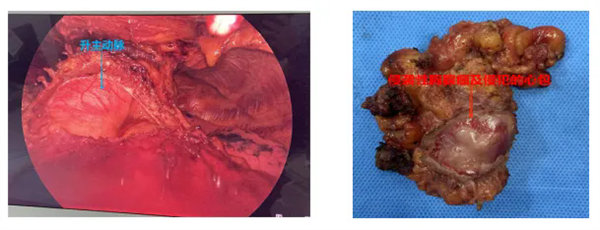

在麻醉手術科陳治富主任團隊的大力支持下,術中緊密合作,精細游離病灶,在狹小的空間下(三個小戳卡孔直徑分別為2cm、0.5cm、0.5cm)小心謹慎的切除受侵犯心包(切除心包后顯露出了主動脈根部、心包內肺動脈部分、心耳等重要結構),最后在充分游離出雙側無名靜脈的前提下切除胸腺上極及兩側心包外脂肪,同時對無名靜脈及上腔靜脈旁淋巴結進行清掃,達到完整切除全胸腺的目的。術后,患者在醫護團隊的精心照料下,恢復情況良好,無并發癥發生。